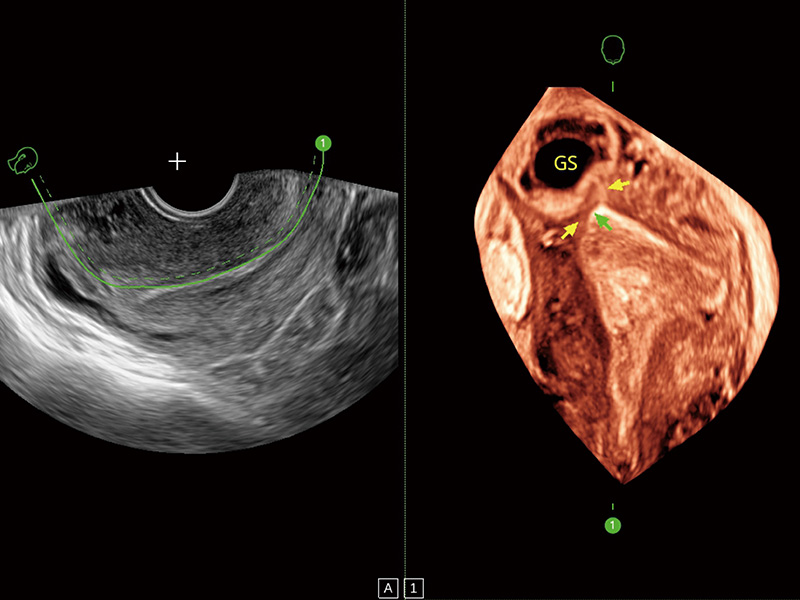

腔内容积探头

腔内三维成像技术获得显著提升,超大扇角在满足日常基础扫查的同时,支持卵泡自动测量及多种三维渲染模式,为您提供更多的诊断信息,尤其是在子宫畸形的诊断,内膜及肿瘤占位观测中起到了重要的作用。

卵巢多囊样改变

中央型宫腔粘连

单角子宫

子宫内膜息肉